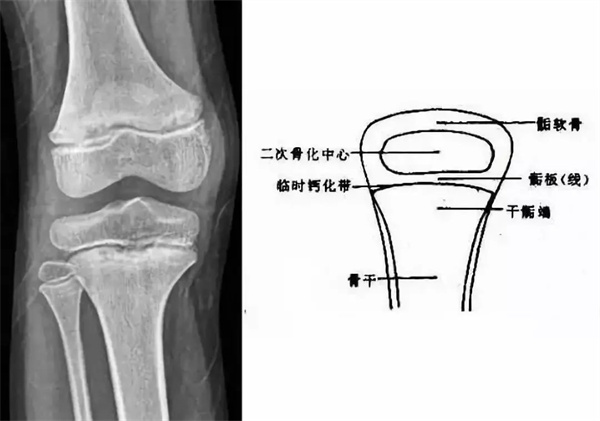

我们都知道,人体的高矮是由骨骼的生长发育决定的,特别是下肢长骨。长骨呈长管状,在长骨的两端有一种专管骨骼生长的骺软骨,它与干骺端之间有一盘状软骨结构称为骺板(线),在幼儿的X光片上表现为一条较宽的透光带。(见下图)

未成年时随着年龄的增加骺软骨端不断骨化,骨骼就不断增长。当骨骺线完全闭合时骨骼就停止生长,个子也就不再增长了。一般骨骺端完全闭合的年龄是18~20岁左右。